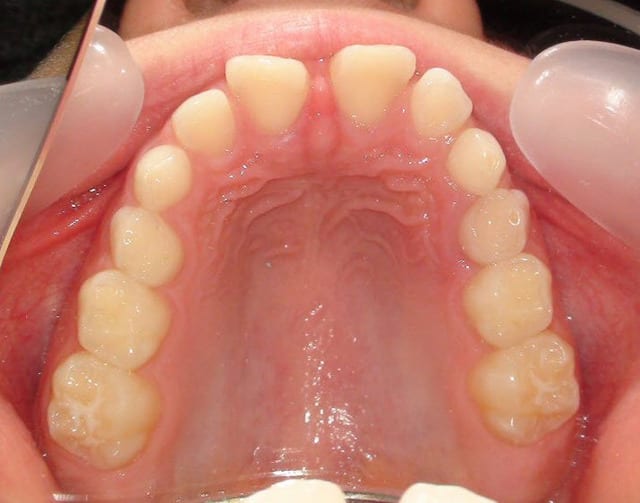

À votre avis, au vu de la téléradio de profil, 13 et 23 sont-elles incluses en vestibulaire ou en palatin ?

Je vous joins également pour faire plaisir à certains des photos intra-buccales bien qu'elles n'apportent absolument rien de plus.

si, si, si, classe d'angle, ddm, supraclusion, volume des arcades, etc...

OK, on voit une supraclusie incisives, mais pas de DDM et j'en aurais parlé dès le départ si ça avait pu apporter quelque chose au plan de traitement.

Et on voit aussi la vestibuloversion de la 22 qui est effectivement un signe positif d'inclusion vestibulaire de la canine. Dans ce sens, tu as raison.